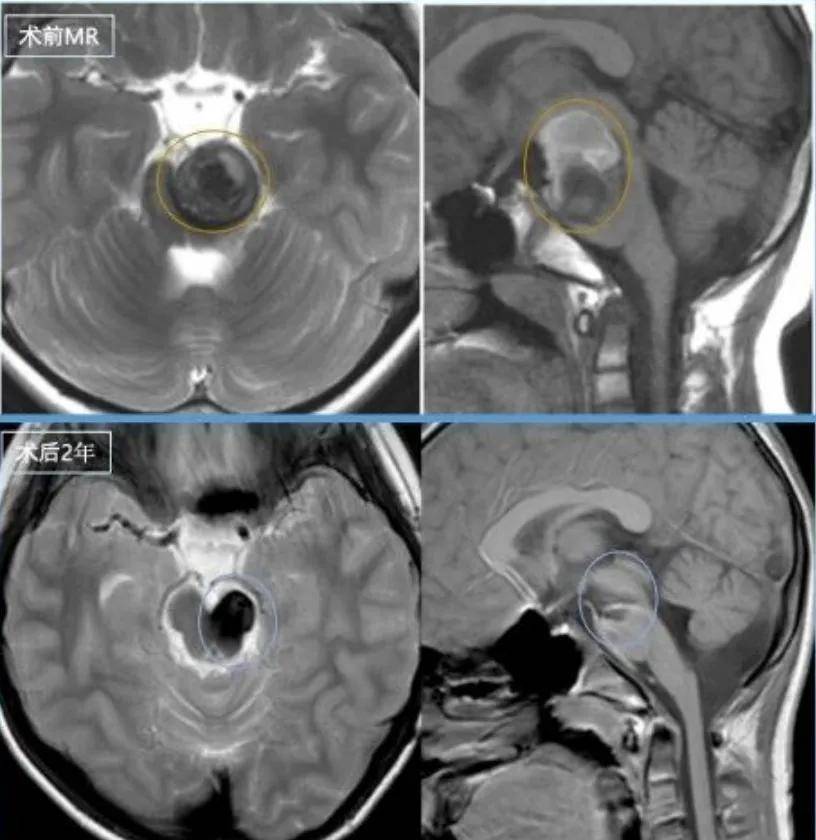

术前情况脑干脑桥偏左侧占位,锥体束受压迫,见含铁血黄素环。

手术当日,巴特朗菲教授采用半坐位手术入路——利用重力减少脑干静脉压力,创造更清晰手术视野。在术中神经电生理监测全程护航下,监测屏幕波形实时反馈神经功能状态。教授精准避开所有关键结构,完整切除血管瘤。

术后当晚,复苏室内阳阳睁开双眼,清晰喊出"妈妈"。术后48小时转出ICU,他用左手捏住父亲纽扣——这一细微主动动作预示运动功能开始恢复。术后第3天,可自主用筷子夹取食物,宣布"我打败怪兽了!"术后第5天,在搀扶下重新迈步。术后3个月,面部瘫痪基本缓解,可小跑追球。

术后三年复查显示无复发

目前术后三年复查显示无复发。额部淡淡疤痕成为男孩勇敢的勋章,他恢复了往日活泼爱笑的性格,但这段经历为他的笑容增添了超越年龄的坚毅。